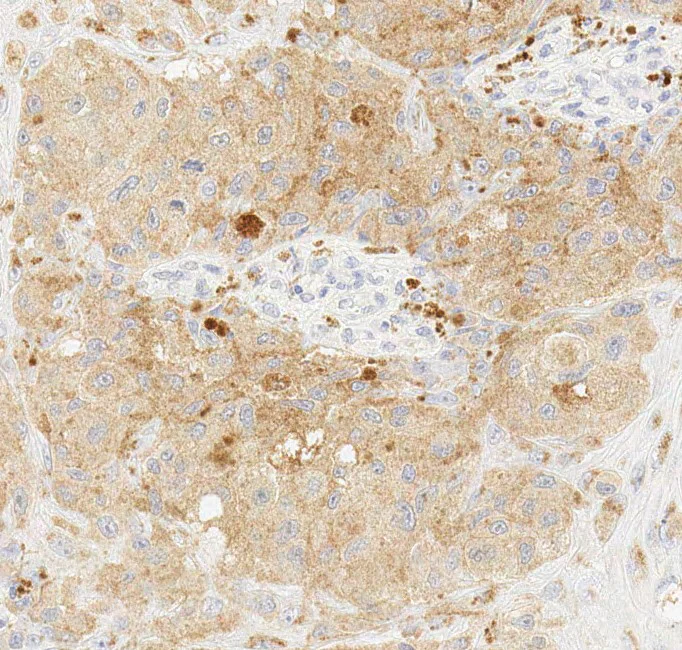

Immunohistochemistry (Formalin/PFA-fixed paraffin-embedded sections) - Anti-BRAF (mutated V600E) antibody [VE1] (AB228461)

Immunohistochemical analysis of formalin fixed paraffin embedded human melanoma labelling BRAF (mutated V600E) with ab228461 at 1/600 dilution. The immunostaining was performed on a Ventana DISCOVERY ULTRA (Roche Tissue Diagnostics) instrument with an OptiView DAB IHC Detection Kit. Heat mediated antigen retrieval was conducted for 32 mins at 100°C with ULTRA cell conditioning solution (CC1, pH 8.5). ab228461 anti-BRAF (mutated V600E) antibody [VE1] was incubated at 37°C for 16 mins. Sections were counterstained with Hematoxylin II. Image inset shows absence of staining in secondary antibody only control.